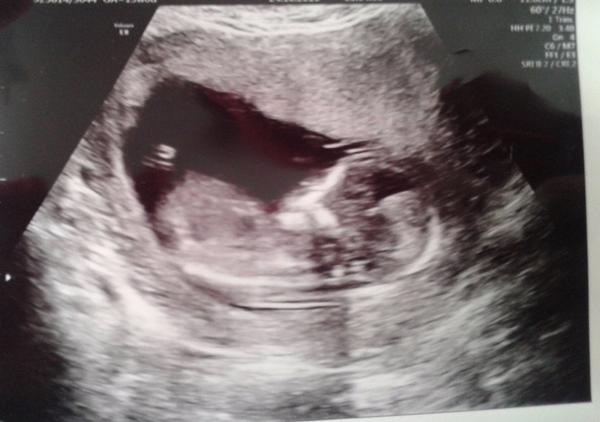

Je to holčička nebo chlapeček? Foto ultrazvuku

Holky, klobouk dolů před těmi, co se v těch fotečkách z ultrazvuku vyznáte, tohle je pro mne naprosto španělská vesnice

@ellilenka já si myslím, že kdyby to byl kluk, tak už by tam pindíka viděli a pokud neviděli, tak je to jasná holčička 🙂 a nebo ještě počkat na další velký utz ve 30.tt a tam si říct ať se zaměří i na pohlaví 🙂 mě to na 100% potvrdili na 4D utz

Děkuji všem za názory. Já si to také myslím, ale co kdyby náhodou 😉 Na další velký ultrazvuk jdu za pět týdnů, tak uvidíme, třeba se konečně pořádně ukáže to malé stvořeníčko 🙂